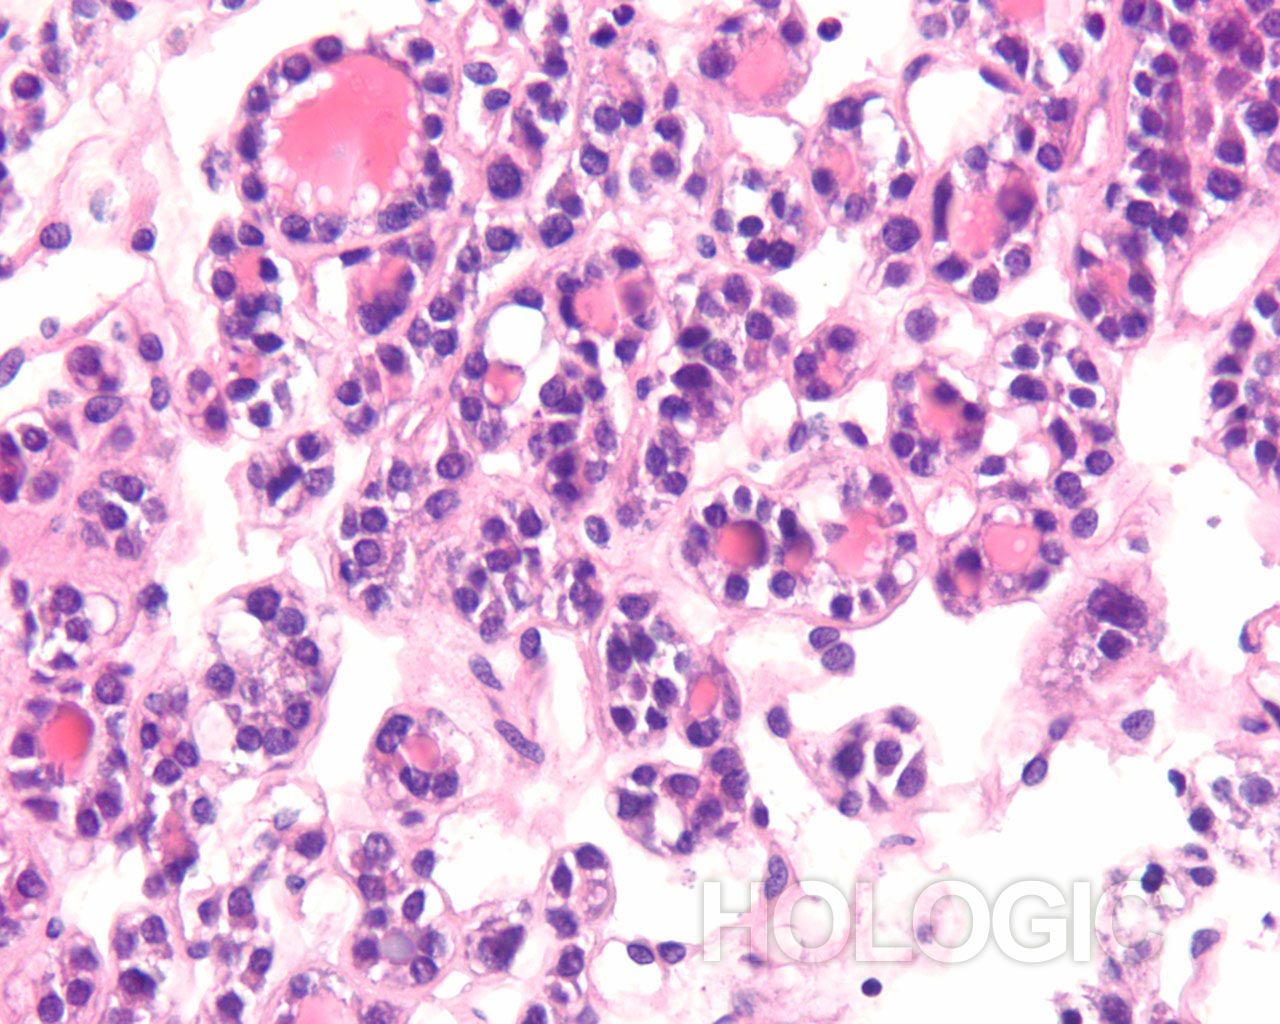

Met celblokken kan de afmeting van de follikel beoordeeld worden op een manier die een aanvulling vormt op de ThinPrep-glaasjes. Om een follikel als groot aan te merken, moeten de folliculaire cellen over een tamelijke grote afstand 2-dimensionaal georganiseerd zijn; als de follikels klein zijn, bevinden de cellen zich niet in een brede 2-dimensionale, platte laag. Het is verrassend moeilijk het eens te worden over de definitie van ‘macrofolliculair’ [9]. Acht tot 10 folliculaire celdiameters lijkt een redelijke definitie voor de macrofolliculaire colloïd fragmenten [9], of voor de diameter van platte, 2-dimensionele macrofolliculaire lagen. In weefselcoupes die loodrecht op een macrofolliculaire groep zijn gesneden, zien de macrofollikels eruit als een lineaire ordening van ten minste 8 folliculaire cellen. Als de sectie in het vlak van een macrofolliculaire groep snijdt, kan men gemakkelijk een solide uitziende celmassa tegenkomen die analoog is aan een weefselcoupe die tangentieel recht door de ductale cellaag snijdt in een schildklier biopsie. Net als pathologen een dergelijke tangentiële coupe kunnen herkennen en kunnen onderscheiden van ductale hyperplasie, kan men een tangentiële coupe door macrofolliculaire groepen herkennen. Dit wordt hieronder geïllustreerd. Microfollikels hebben per definitie een hoge ratio tussen de cellen en het colloïd en de cellen kunnen niet in een brede 2-dimensionele laag liggen. In celblokcoupes vertonen microfollikels geen lange lineaire organisatie van cellen. Renshaw et al. vonden een significante grijze zone onder experts in het onderscheid tussen microfolliculaire en macrofolliculaire groeperingen op cytologische preparaten [9].Een van de belangrijkste grijze gebieden betreft het probleem van folliculaire cellen die artefactueel op elkaar zijn gestapeld. Deze artefactuele stapeling van cellen lijkt gemakkelijker te diagnosticeren in weefselcoupes. Een ander probleemgebied betreft die gevallen waarin microfollikels en macrofollikels door elkaar zijn gemengd. Het is ons en anderen opgevallen dat benigne stromanodulen vaak plat cytoplasma vertonen in de cellen van de microfollikels. De robuustere cellen van een folliculair neoplasma tonen vaak veelal kubusvormige of zelfs cilindrische, folliculaire cellen die de microfollikels bekleden [7]. Deze kenmerken zijn duidelijk in celblokcoupes en worden hieronder geïllustreerd.

Benigne folliculaire nodulen vertonen vaak een bijmenging van cytologisch verschillende typen folliculaire cellen. De follikels van folliculaire neoplasmen zijn meestal uniform van aard. Hoewel het uiterlijk van de follikels in een cytologisch preparaat van groep tot groep kan worden vergeleken, kan deze benadering van het beoordelen van de klonaliteit soms moeilijk zijn. Het kan bijvoorbeeld onmogelijk zijn om te weten of de FNA-naald buiten het neoplasma monsters heeft genomen. Met celblokken kunnen de morfologische kenmerken van waarlijk aangrenzende follikels over een bereik van enkele honderden microns geëvalueerd worden, zoals hieronder geïllustreerd wordt.

Papillair schildkliercarcinoom is een gemakkelijke diagnose als de nucleaire kenmerken goed ontwikkeld zijn en het monster goed is gepreserveerd. De beste diagnostische kenmerken van papillair schildkliercarcinoom zijn fijn verdeeld chromatine en een onregelmatige nucleaire envelop[2]. Het is interessant dat papillair schildkliercarcinoom het eerste voorbeeld is van een kanker waarbij de diagnostische nucleaire kenmerken rechtstreeks gerelateerd zijn aan de genen die de kanker veroorzaken (besproken in [10]). Een reeks van verschillende onregelmatigheden van de nucleaire envelop kan aanwezig zijn [11]. De chromatine van een papillair schildkliercarcinoom is verdeeld in erg fijne deeltjes en aangezien een groot deel van de chromatine gelijkmatig aan de nucleaire envelop kleeft, heeft zelfs een kleine vouw als gevolg dat de chromatine in de nucleaire envelop er uitziet als een lineair aggregaat of een langwerpige groef. Vooral intranucleaire cytoplasmische inclusies zijn kenmerkend voor een papillair schildkliercarcinoom, maar deze kunnen ook worden aangetroffen bij medullaire schildkliercarcinoom. Deze intranucleaire cytoplasmische inclusie ziet eruit als een scherpe demarcatie die afkomstig is van het heterochromatine in de nucleaire envelop, waardoor het een duidelijke donkerpaarse begrenzing van het cytoplasma vormt. Intranucleaire cytoplasmische inclusies komen zelden voor bij folliculaire neoplasmen [2].

Folliculaire neoplasmen tonen in tegenstelling tot een papillair schildkliercarcinoom compacte aggregaten van heterochromatine. Het is onze ervaring dat de kern van een papillair carcinoom grofweg kan worden onderscheiden van kernen van folliculaire carcinomen, doordat papillaire schildkliercarcinomen vaak meer lineaire aggregaten chromatine vertonen (erg oppervlakkige vouwen van de nucleaire envelop) dan ronde of geklonterde chromatinemassa’s. Deze kenmerken worden hieronder geïllustreerd.